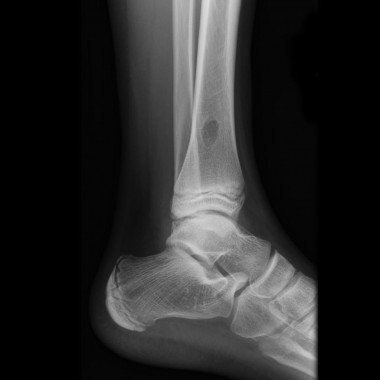

Fibrome non ossifiant

Publié 14 juillet 2015 à 1024 × 1024 dans Tumeurs os – Fibrome non ossifiant

Radiographies

Case courtesy of Dr Frank Gaillard, Radiopaedia.org. From the case Fibrous cortical defect